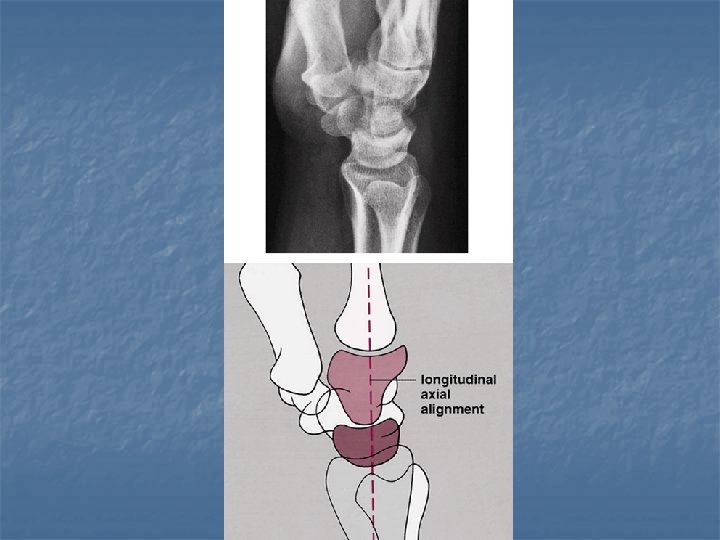

Normal anatomical relations n Lateral view with wrist in neutral position: radius, lunate, capitate, 3 rd metacarpal should be in the same line.

Normal anatomical relations n Dorsovolar view with wrist in neutral postion: 3 smooth unbroken arcs should be seen (Gilula arcs) Arc I: proximal articular surfaces of the scaphoid, lunate, & triquetrum n Arc II: distal concavities of scaphoid, lunate, & triquetrum n Arc III: proximal convexities of capitate & hamate n